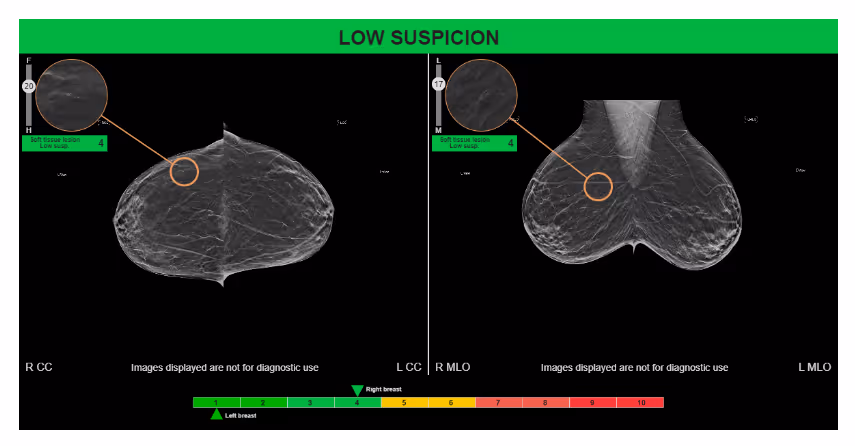

Ferrum Health partners with best-in-class AI providers offering solutions designed to reduce radiology workload and improve patient care.Therapixel Case Study: AI Helps to Avoid False Positive RecallIntroductionA clinical study, reviewing a benign diagnosis, compared the performance of radiologists reading with and without MammoScreen® 3D. Clinical StudyClustered microcalcifications in the upper outer quadrant at the junction of the middle and posterior third of the breast were identified on a baseline mammogram by the original reader. A follow-up exam recommended a stereotactic biopsy of the microcalcifications. Results diagnosed the area of microcalcifications and surrounding tissue as benign.MammoScreen correctly flagged this cluster on the mammogram with a score of 4 (low suspicion). During a reader study, 5 radiologists did not recall this case unassisted against 12 utilizing MammoScreen. Moreover, utilizing MammoScreen reduced the reading time on average by 29%.